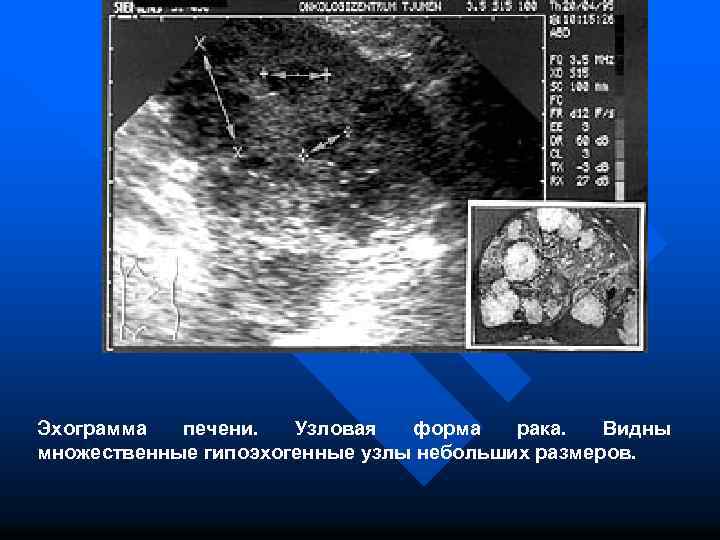

Эхограмма печени. Узловая форма рака. Видны множественные гипоэхогенные узлы небольших размеров.